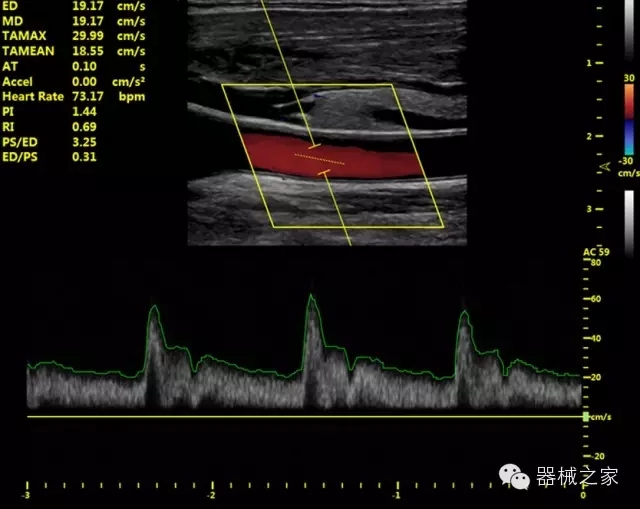

·獨有的HoloTM PW 實時3取樣門PW成像技術(shù),精確進行血管診斷;